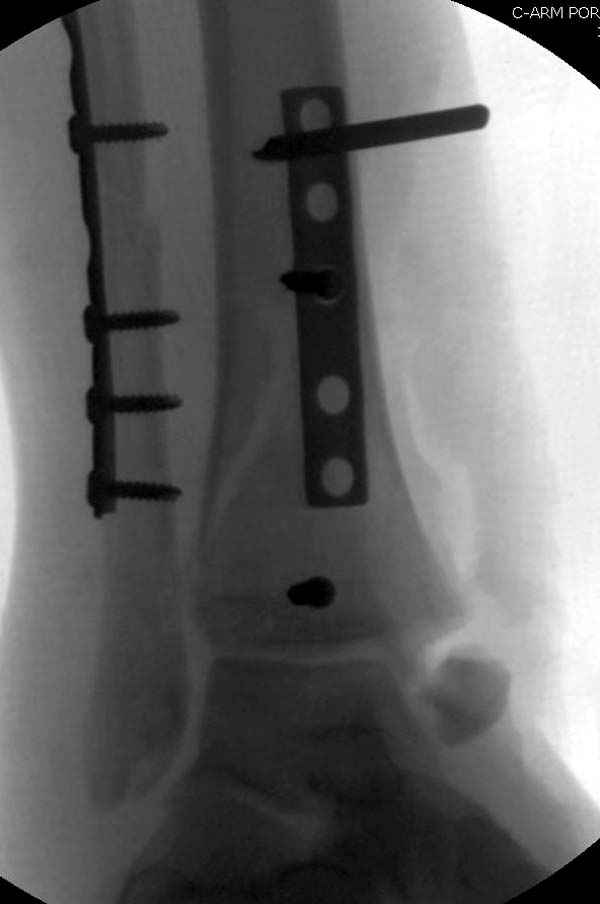

По снимкам довольно сохранный сустав, и такой сустав желательно попытаться восстановить всеми возможными мерами.

Насчет пилона, прошло достаточное время для консолидации и прекрасная возможность для демонстрации, что такие случаи могут быть успешно вылечены остеотомией, несмотря на засторелость.

Из заднего доступа остеотомия тонким остеотомом и коррекции на ЭОПе.

Без применения сложной конструкции, а обычными параллельными шурупами. Шурупы в 3.5 мм и дополнительно фиксация крючковидной пластиной, сделанной из 3.5 mm semitubular пластиной, Butress или аntiglade фиксация.

Здесь алгоритм фиксации свежего перелома и преоперационный план для обсуждаемого случая.